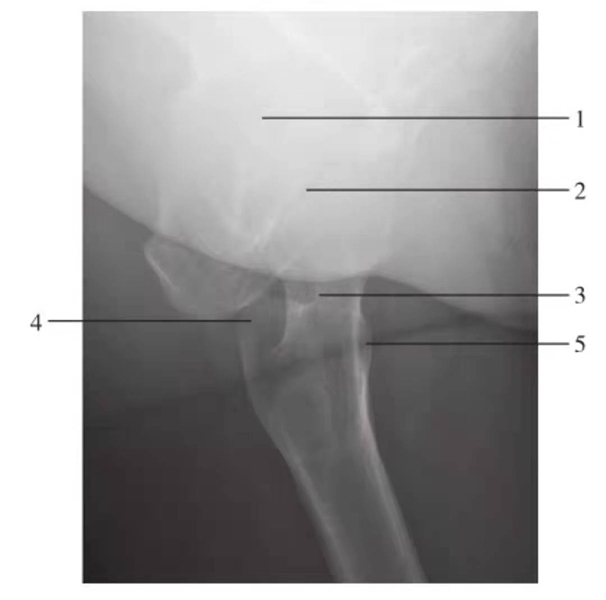

图3 髋关节和股骨颈侧位

1.髋臼;2.股骨头;3.股骨颈;4.大转子;5.小转子